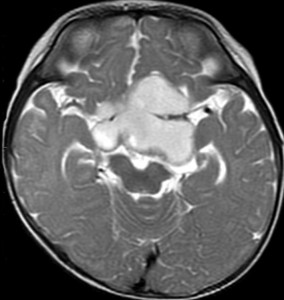

生後7カ月の幼児です。目が揺れるようになり(振り子様眼振)眼科を受診して腫瘍が発見されました。小児脳腫瘍の治療ができる病院へと紹介されました。

1ヶ月後にまたMRI検査がされました。乳児ですから検査にも麻酔が必要です。腫瘍は明らかに大きくなっています。左視神経から視索の腫瘍化が著しいので右側だけかすかに視力が残っているかもしれません。視力は明かりがわかる程度(明暗弁)と評価されました。